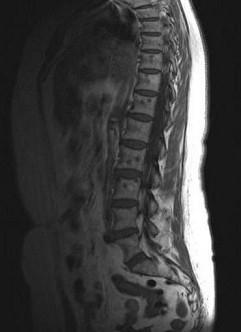

问题 女,57岁,背部隐痛1个月余,请结合影像学检查,选出最可能的诊断 ( )

选项 A、椎体压缩骨折 B、脊椎转移瘤 C、脊椎结核 D、强直性脊柱炎 E、化脓性脊柱炎

答案 B